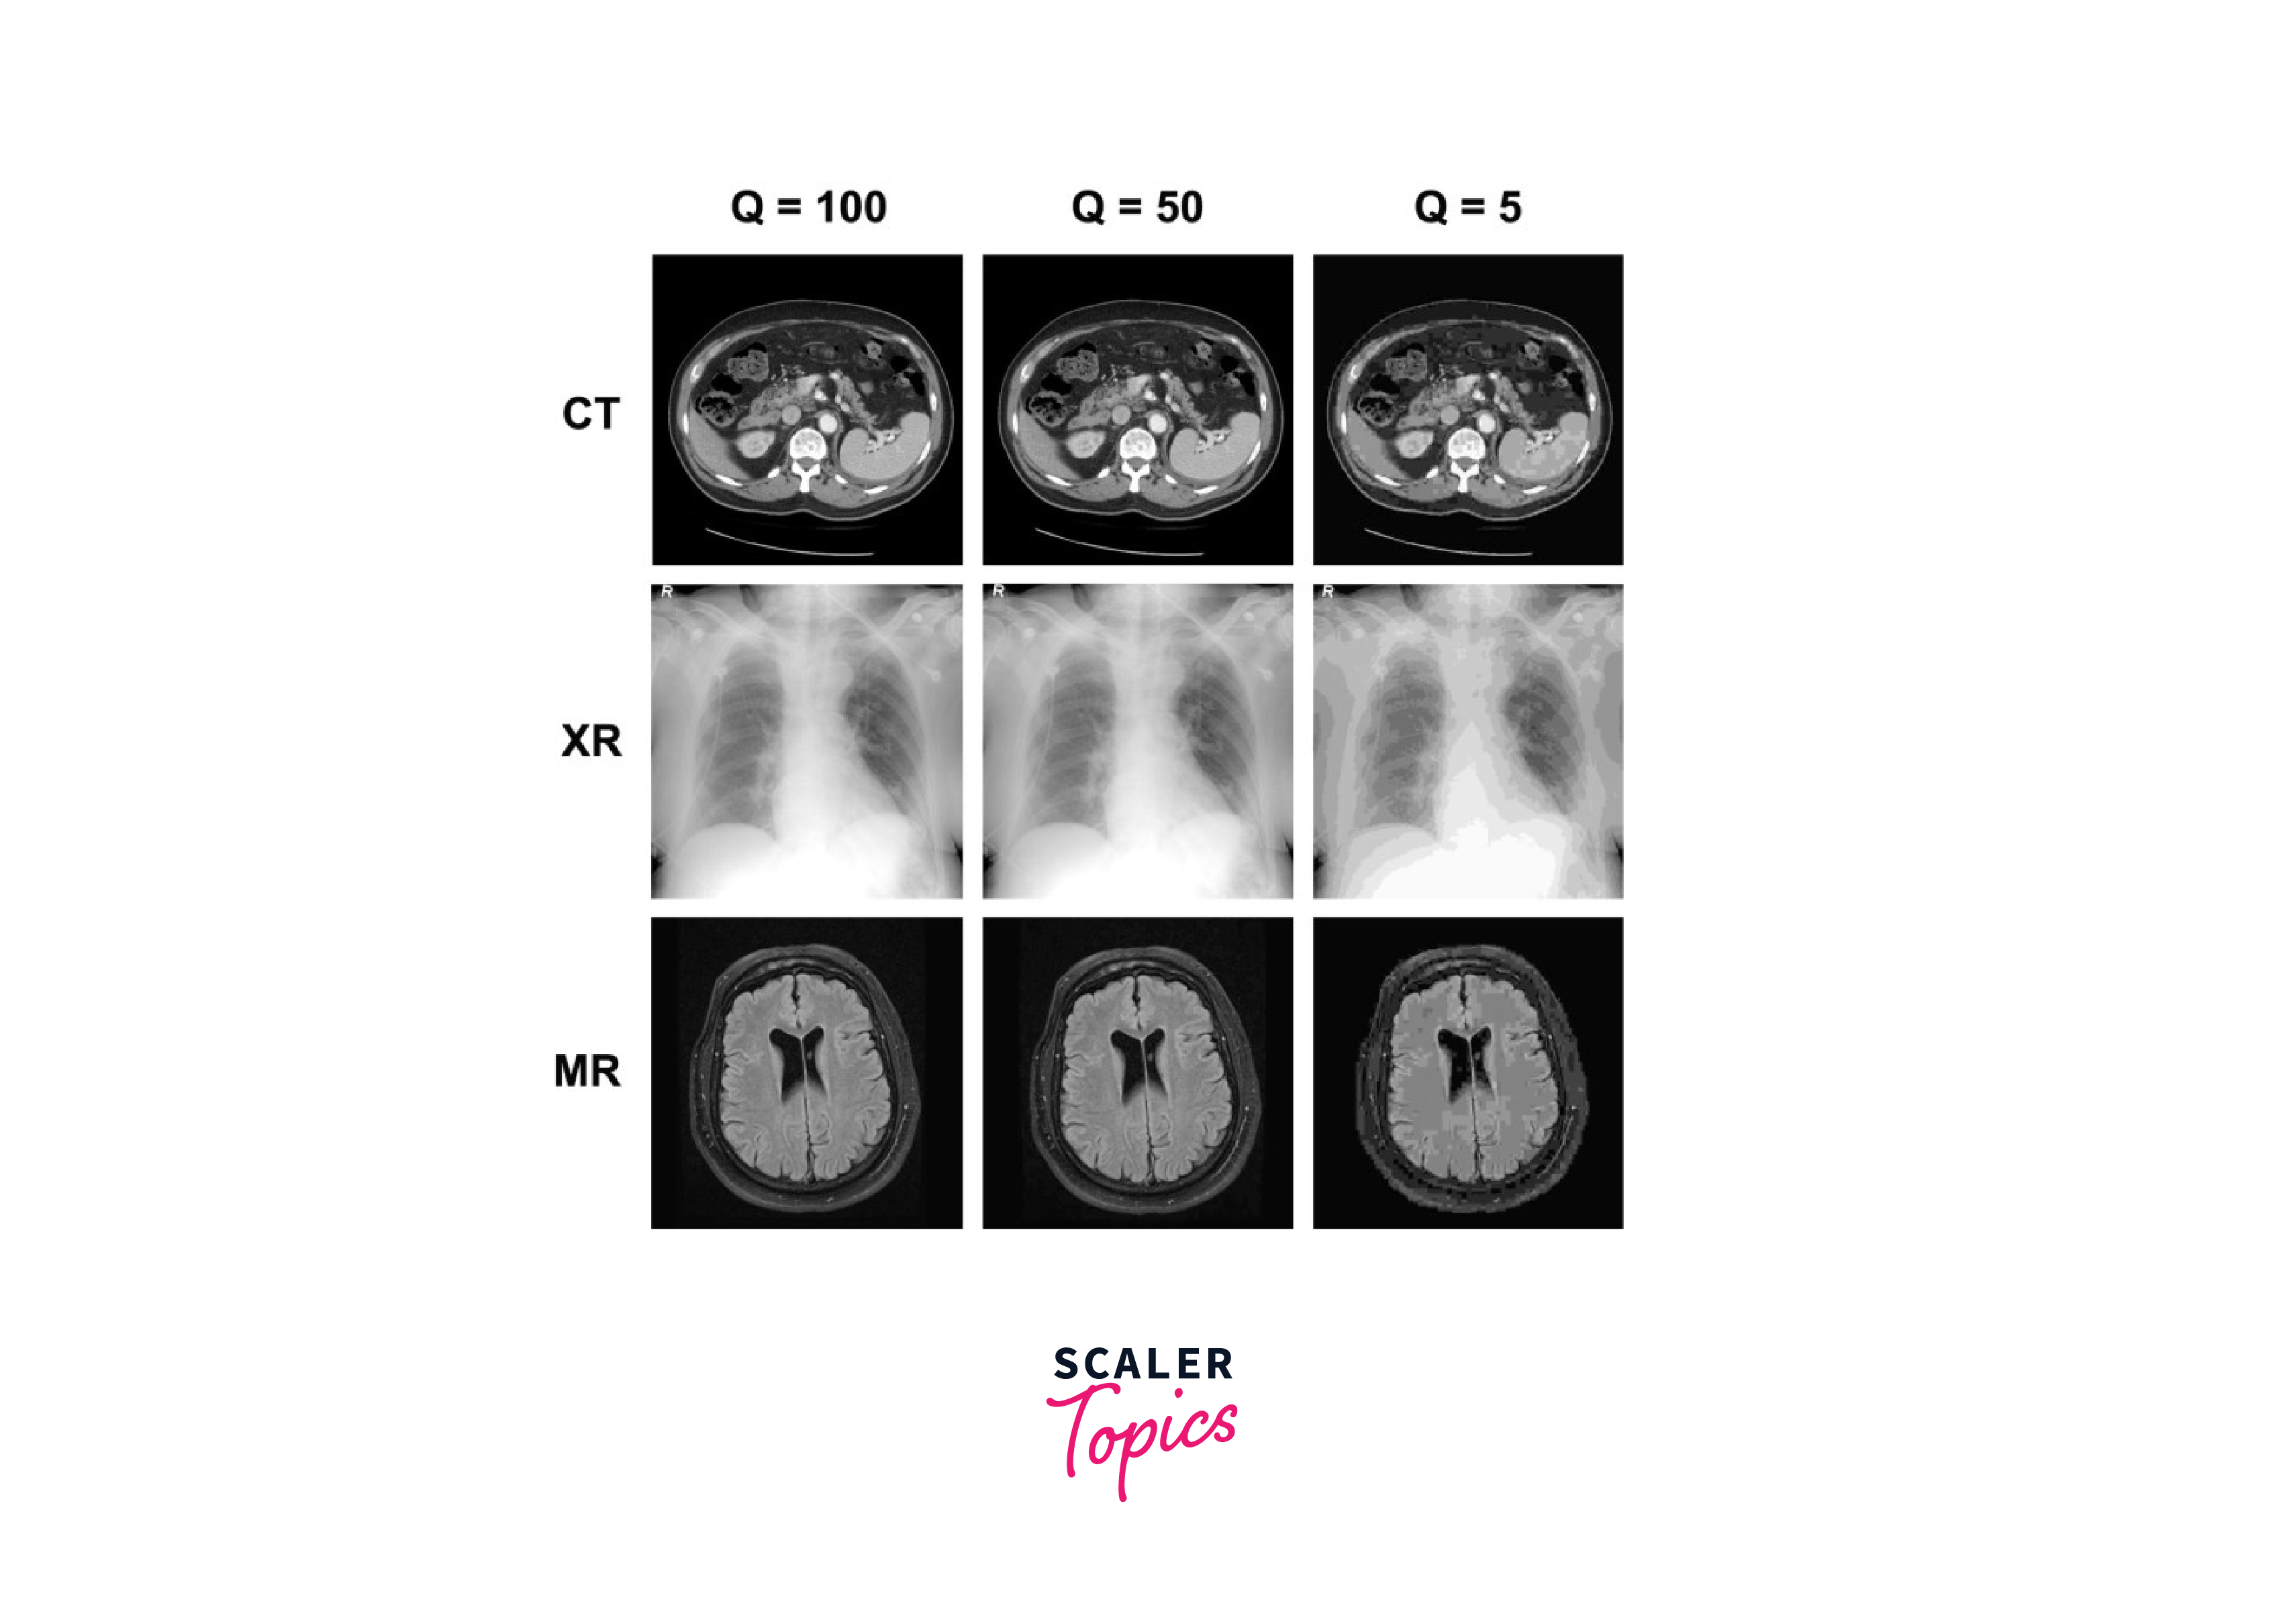

1. Medical Imaging: To ensure precise diagnosis and treatments, it is crucial to keep all of the data in medical imaging. Medical pictures are frequently compressed while retaining their diagnostic value using lossless compression methods, such as those found in the DICOM standard.

4. Scientific Data: Because it enables effective storage and transmission of big data sets, lossy compression is frequently used for scientific data, including satellite photos and medical scans. Lossy compression techniques can shrink data files without considerably compromising their scientific correctness.

The particular compression technique utilised, the amount of compression employed, and the kind of data being compressed all affect how much quality is lost. For instance, audio files compressed using the MP3 technique may show a loss of high-frequency information or a "swishing" sound, while pictures compressed with the JPEG algorithm may show visual artefacts, such as blockiness or colour distortions.

Medical Imaging: The original data must be kept in medical imaging applications without any information being lost. To decrease the amount of storage needed while keeping the original data, lossless compression is performed.

Medical Imaging: Imaging in the medical field generates a lot of data that needs to be efficiently stored and delivered. Medical image compression uses lossless compression methods like DICOM to guarantee that no data is lost during the process.

Medical Imaging: Imaging in the medical field generates a lot of data that needs to be efficiently stored and delivered. Medical image compression uses lossless compression methods like DICOM to guarantee that no data is lost during the process. For a proper diagnosis and course of therapy, this is essential.